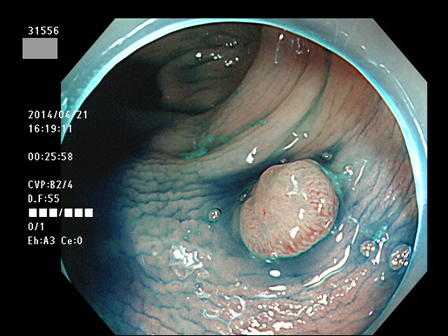

上記100名より抽出した平坦・陥凹型腺腫(=癌化の危険が高いが見落としやすい病変)の内視鏡写真

31532 31533 31534(SSA/Pのみ) 31537 31538 31539 31540 31541 31542 31545 31546 31550 31552 31553 31554 31555 31556 31562(SSA/Pのみ) 31563 31564 31565 31566 31567 31572 31573 31574 31576 31578 31579 31580 31581 31582 31586 31587 31589 31590 31591 31593 31596 31597 31598 31599 ・・・・の65名